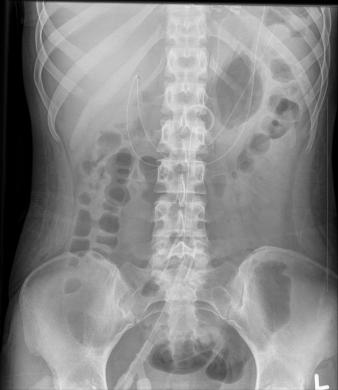

X-Ray showing my tube placement. The small circle on my spine is where the number is and the loop on the right hand side of the photo is where the tube loops in my stomach.